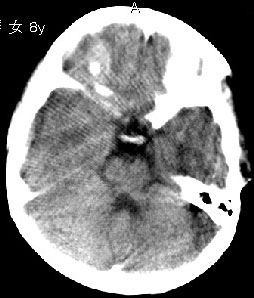

杨某,女,8y,家长述2006.10.13行破伤风疫苗注射后下肢疼痛,后自行粘贴膏药未见好转

,后续发现左上肢肢力下降。于2006.10.28在我院行ct检查,发现右侧基底节区片状低密度影,

无占位效应。ct值约:18~20hu。边界清晰,与相邻脑室无通连。未行增强扫描。余脑实质

未见异常。

右侧内囊后支、丘脑见片状低密度区,边界不清,无占位效应。

从ct图像看,准确地说病变是在右侧丘脑,累积右侧内囊后肢。